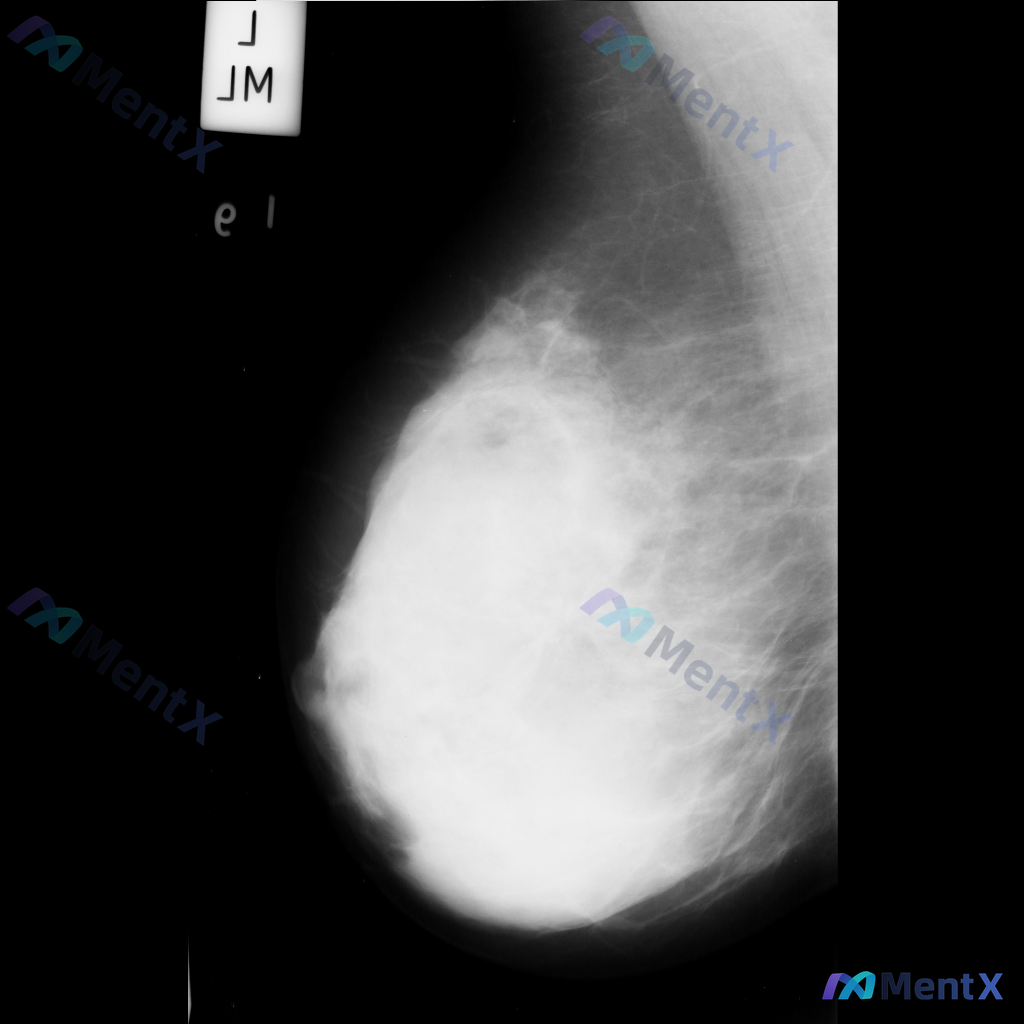

这张乳腺钼靶影像的异常表现,最适合用什么术语描述?

整理到一张乳腺钼靶影像资料,大家一起讨论下。 影像表现大概是这样: - 异常区域位于乳腺下象限偏外侧 - 可见一局限性致密影,形态大致呈卵圆形或不规则形 - 边缘部分清晰,局部可能模糊或有细微毛刺样改变 - 致密影密度高于周围脂肪组织,与纤维腺体组织密度相似或略高 - 周围乳腺小梁结构似有轻微的牵拉...

整理到一张乳腺钼靶影像的读片讨论资料: 影像显示右乳腺局部区域存在一不规则高密度肿块,伴有毛刺状边缘及局灶性结构扭曲。 想先跟大家讨论一下:单看这组特征,你首先会往哪个方向考虑?后续又会建议如何处理?

今天看到一个很有代表性的病例,整理出来和大家分享一下,把分析思路也梳理清楚了 病例基本信息 - 患者:39岁非裔美国女性 - 主诉:癫痫发作伴严重发作后头痛入院 - 既往史:1年前确诊2B期浸润性乳腺癌,当时表现为乳房坚硬、岩石状、不可移动、边界不规则肿块,伴随乳房皮肤红斑、凹陷,同侧活动性腋窝淋巴...

整理到一张乳腺钼靶影像资料,可见一处明确的异常表现: - 局部有形态不规则的占位性病灶,密度高于周围正常腺体组织 - 病灶边缘有细小的放射状结构向周围延伸 - 病灶周围的乳腺腺体和纤维组织结构排列紊乱 另外,该病例的乳腺组织整体密度较高(不均匀致密型)。 想和大家讨论:对于这张影像的异常表现,用哪些...